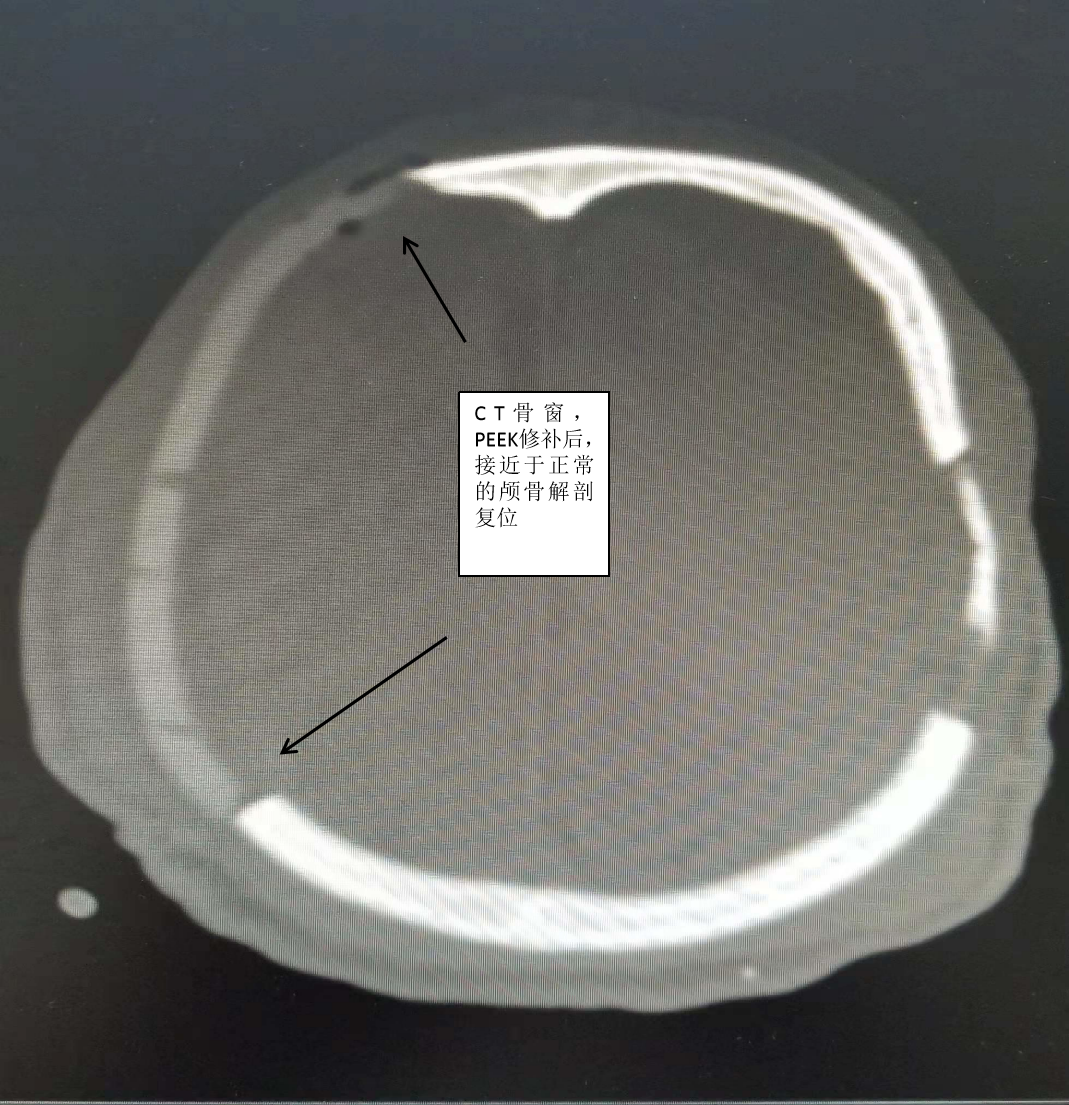

PEEK是一种什么材料?为什么它应用于颅骨修补术后会让一个国家的人民喜大普奔呢?重型颅脑损伤往往会去骨瓣减压,去骨瓣后往往会留有颅骨缺损,后期一般会行颅骨修补术,而修补材料的选择是一个大问题,从一开始的应用骨水泥、自体骨,到肽网等材料,这些材料各有优缺点,而且许多材料缺点非常明显。而PEEK(学名聚醚醚酮)是一种新型的工程塑料,应用于颅骨修补术是一个历史的飞跃。PEEK到底有什么优点呢?1、跟颅骨一样的厚度,硬度高,抗撞击不易变形,不导热,三维成形后镶嵌于颅骨缺损处,而不是向肽网那样覆盖予颅骨缺损处,再用连接板固定于颅骨,手术后的效果近乎完美。2、适用于各年龄阶段,尤其适合12岁以下的儿童,而目前最常用的肽网因儿童颅骨的继续发育不能使用。3、PEEK修补术后可以行核磁共振检查,而目前普通的钛网材料不能行核磁共振检查。

目前兰陵县人民医院颅脑创伤外科已经完成了12例此种手术,全部成功,无一例感染。此手术相对于单纯的肽网覆盖手术来说有更严格的要求,要具备更高超的手术技巧,在这方面兰陵县人民医院颅脑创伤外科已经积累了丰富的经验,在全市医院当中名列第一。